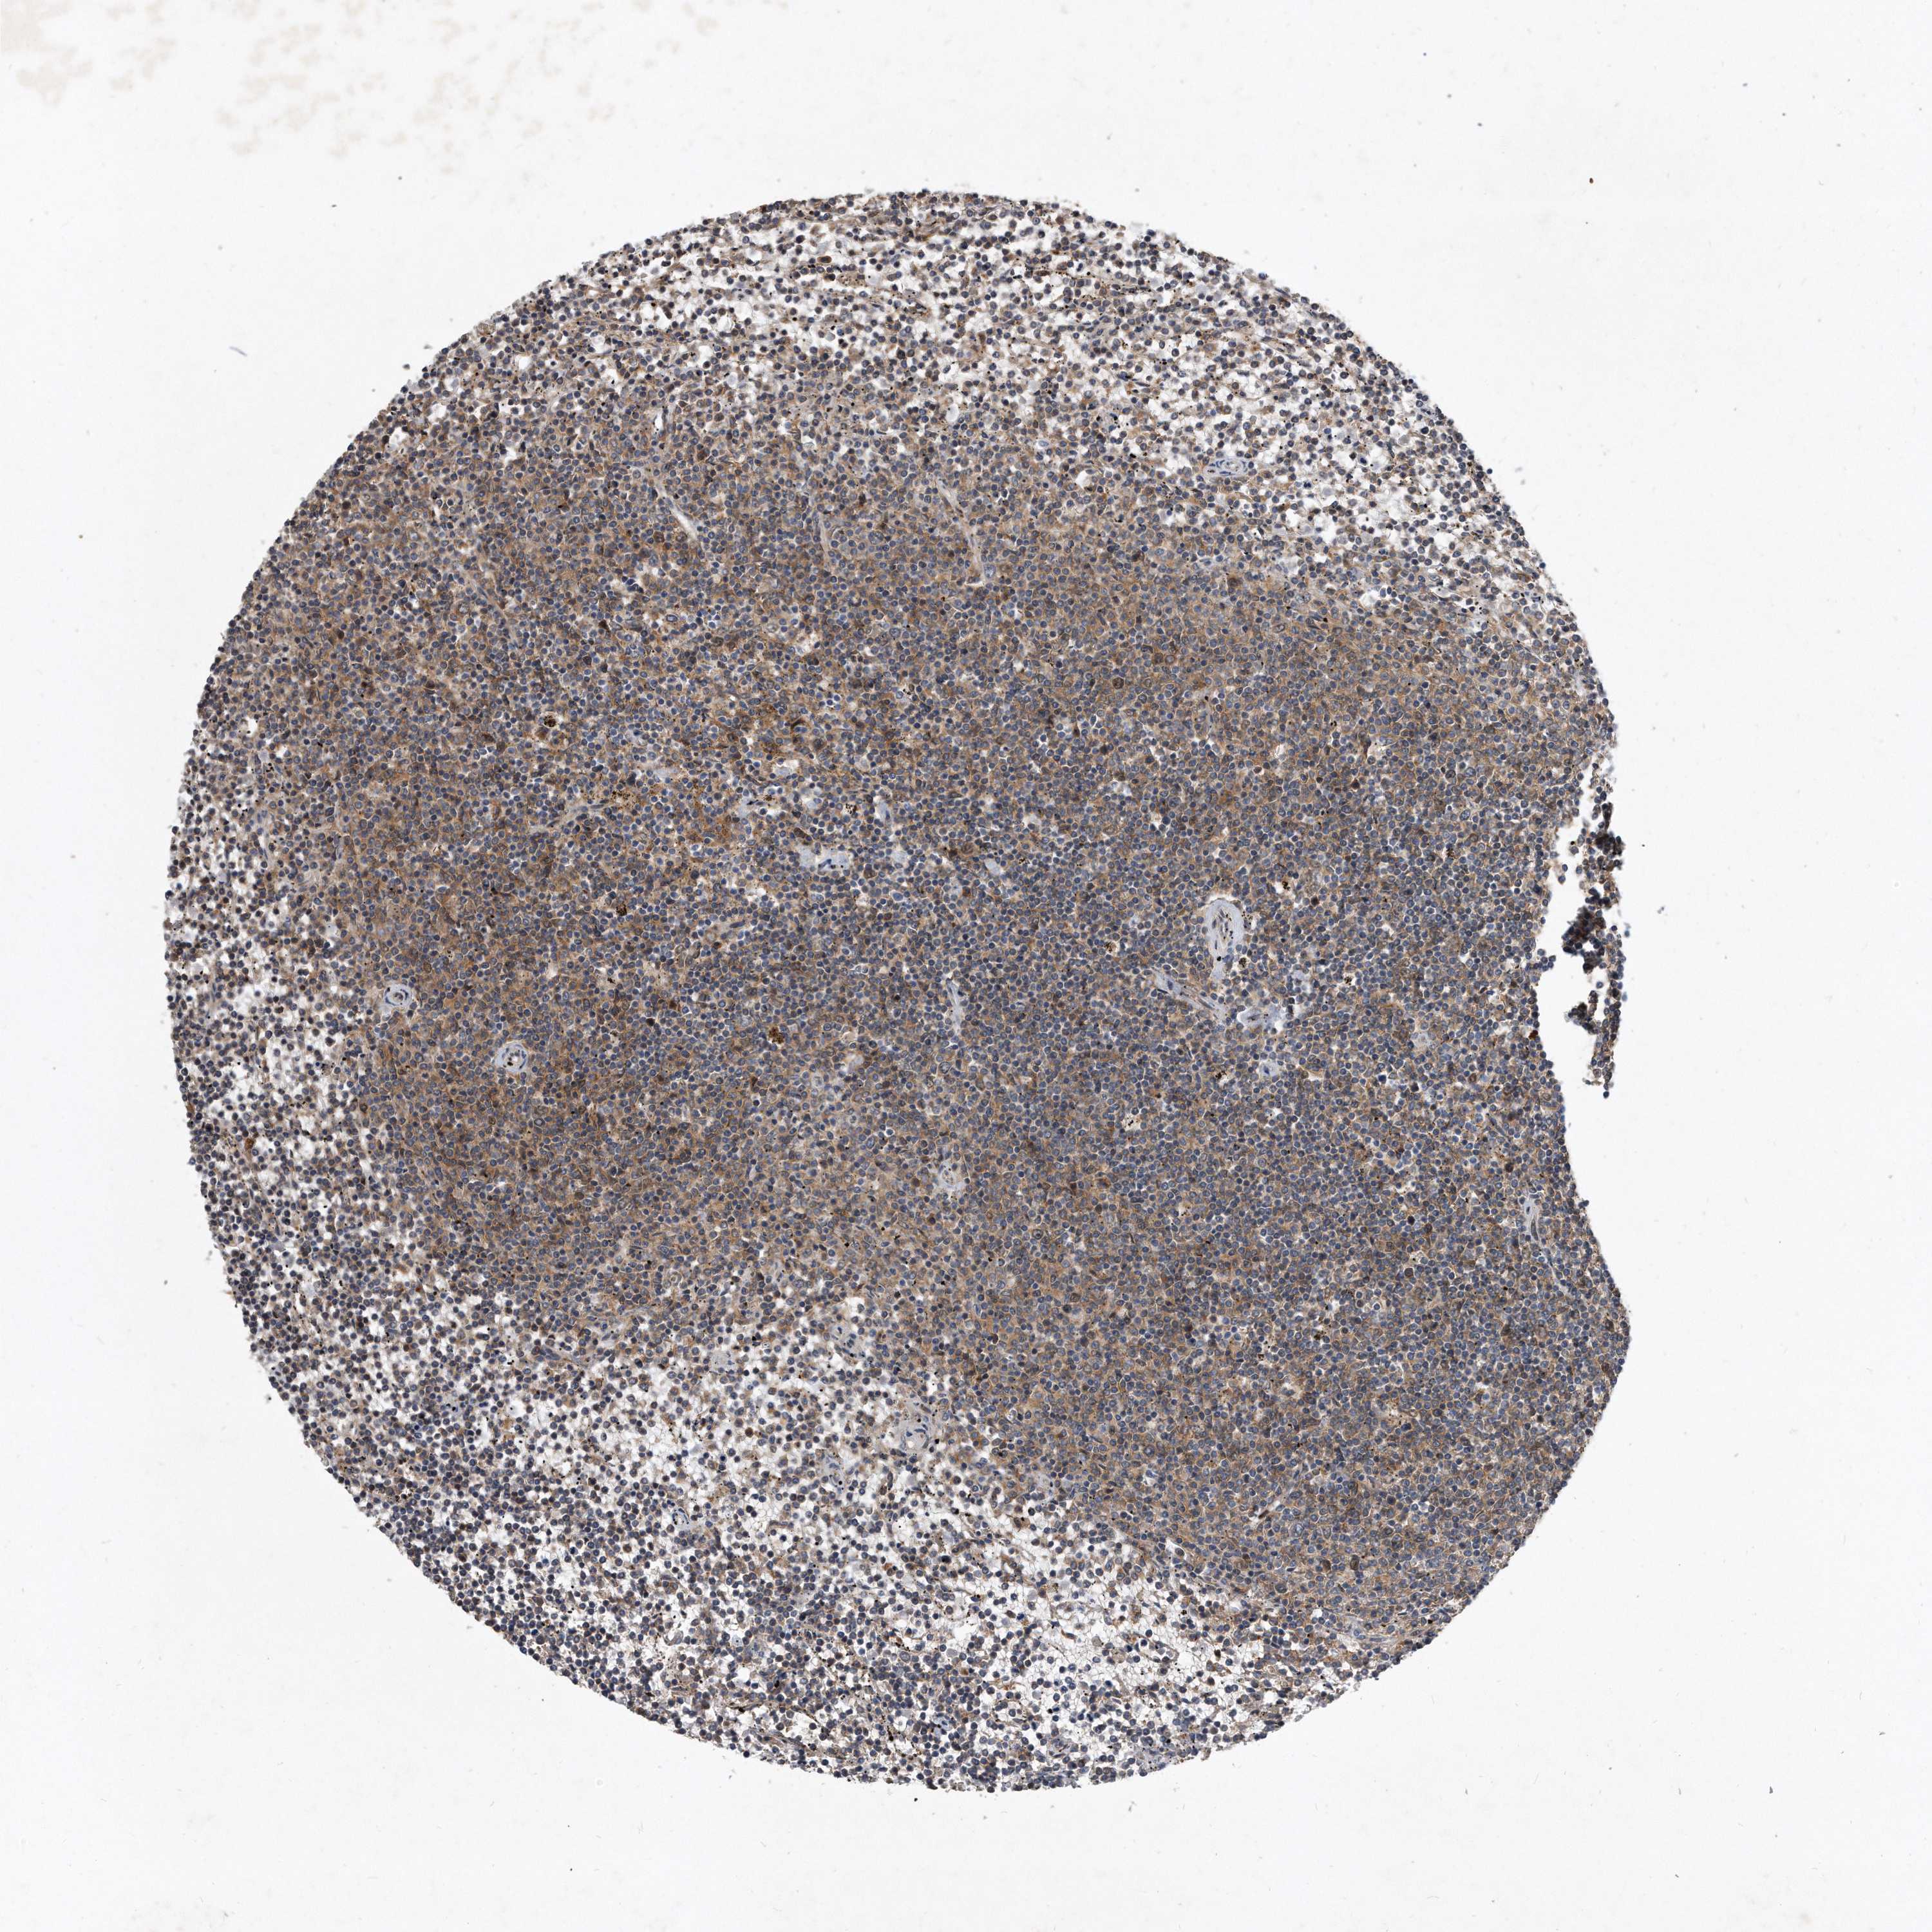

LYMPHOMA - Protein expressioni

A mouse-over function shows sample information and annotation data. Click on an image to view it in a full screen mode. Samples can be filtered based on level of antibody staining by selecting one or several of the following categories: high, medium, low and not detected. The assay and annotation is described here.

Antibody stainingi

Antibody staining in the annotated cell types in the current human tissue is reported as not detected, low, medium, or high, based on conventional immunohistochemistry profiling in selected tissues. This score is based on the combination of the staining intensity and fraction of stained cells.

Each image is clickable and will lead to virtual microscopy that enables deeper exploration of all samples and also displays staining intensity scores, fraction scores and subcellular localization as well as patient and tissue information for each sample.

Antibody HPA029888

Antibody HPA029889

Antibody HPA029890

Hodgkin's disease, NOS

Malignant lymphoma, non-Hodgkin's type, High grade

Malignant lymphoma, non-Hodgkin's type, Low grade